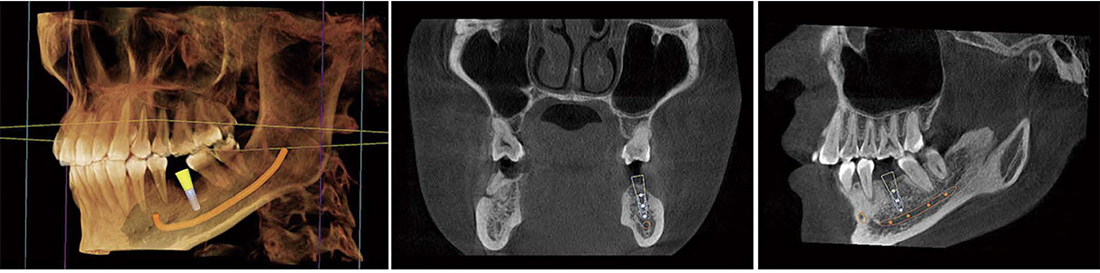

Planificación de la cirugia de implantes

Representación del tubo neural

- Comprobar la dirección del tubo neural y su relación con la posición de las muelas del juicio

- Comprobar la distancia entre el tubo neural y el implante para evitar que el implante toque el tubo neural

Siembra simulada

- DViewMatrix ha agregado un nuevo modulo de implante de simulación 30, que puede medir el ancho, la altura y la densidad ósea de los dientes faltantes y el hueso alveolar, y también puede realizar la delineación del tubo neural.

- Rica biblioteca de implantes

- Introducir parametros de implante simulados y diseñar un plan de implante simulado.

Medición de la densidad ósea

- Medir la osteoporosis y proporcionar referencia para la implantaci6n.